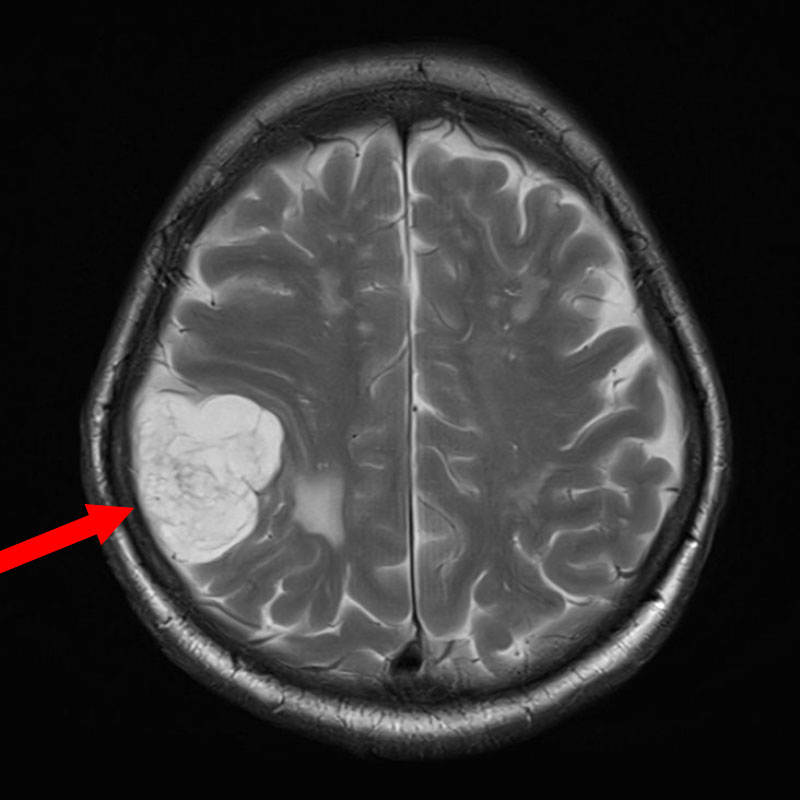

625

'25年4月

60代

円蓋部髄膜腫

頭蓋内腫瘍摘出術

No.’25_27 手術前1

No.’25_27 手術前2